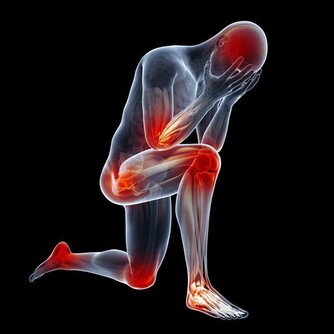

然而,當病情變得更加嚴重時,會導致腹痛、疲勞、極度疲倦、不明原因的體重減輕和虛弱。如果肝硬化發展,患者可能出現嚴重症狀,比如皮膚和眼白色變黃,腿部、腳踝、腳或肚子腫脹。然而等到那時候,就已經太晚了。